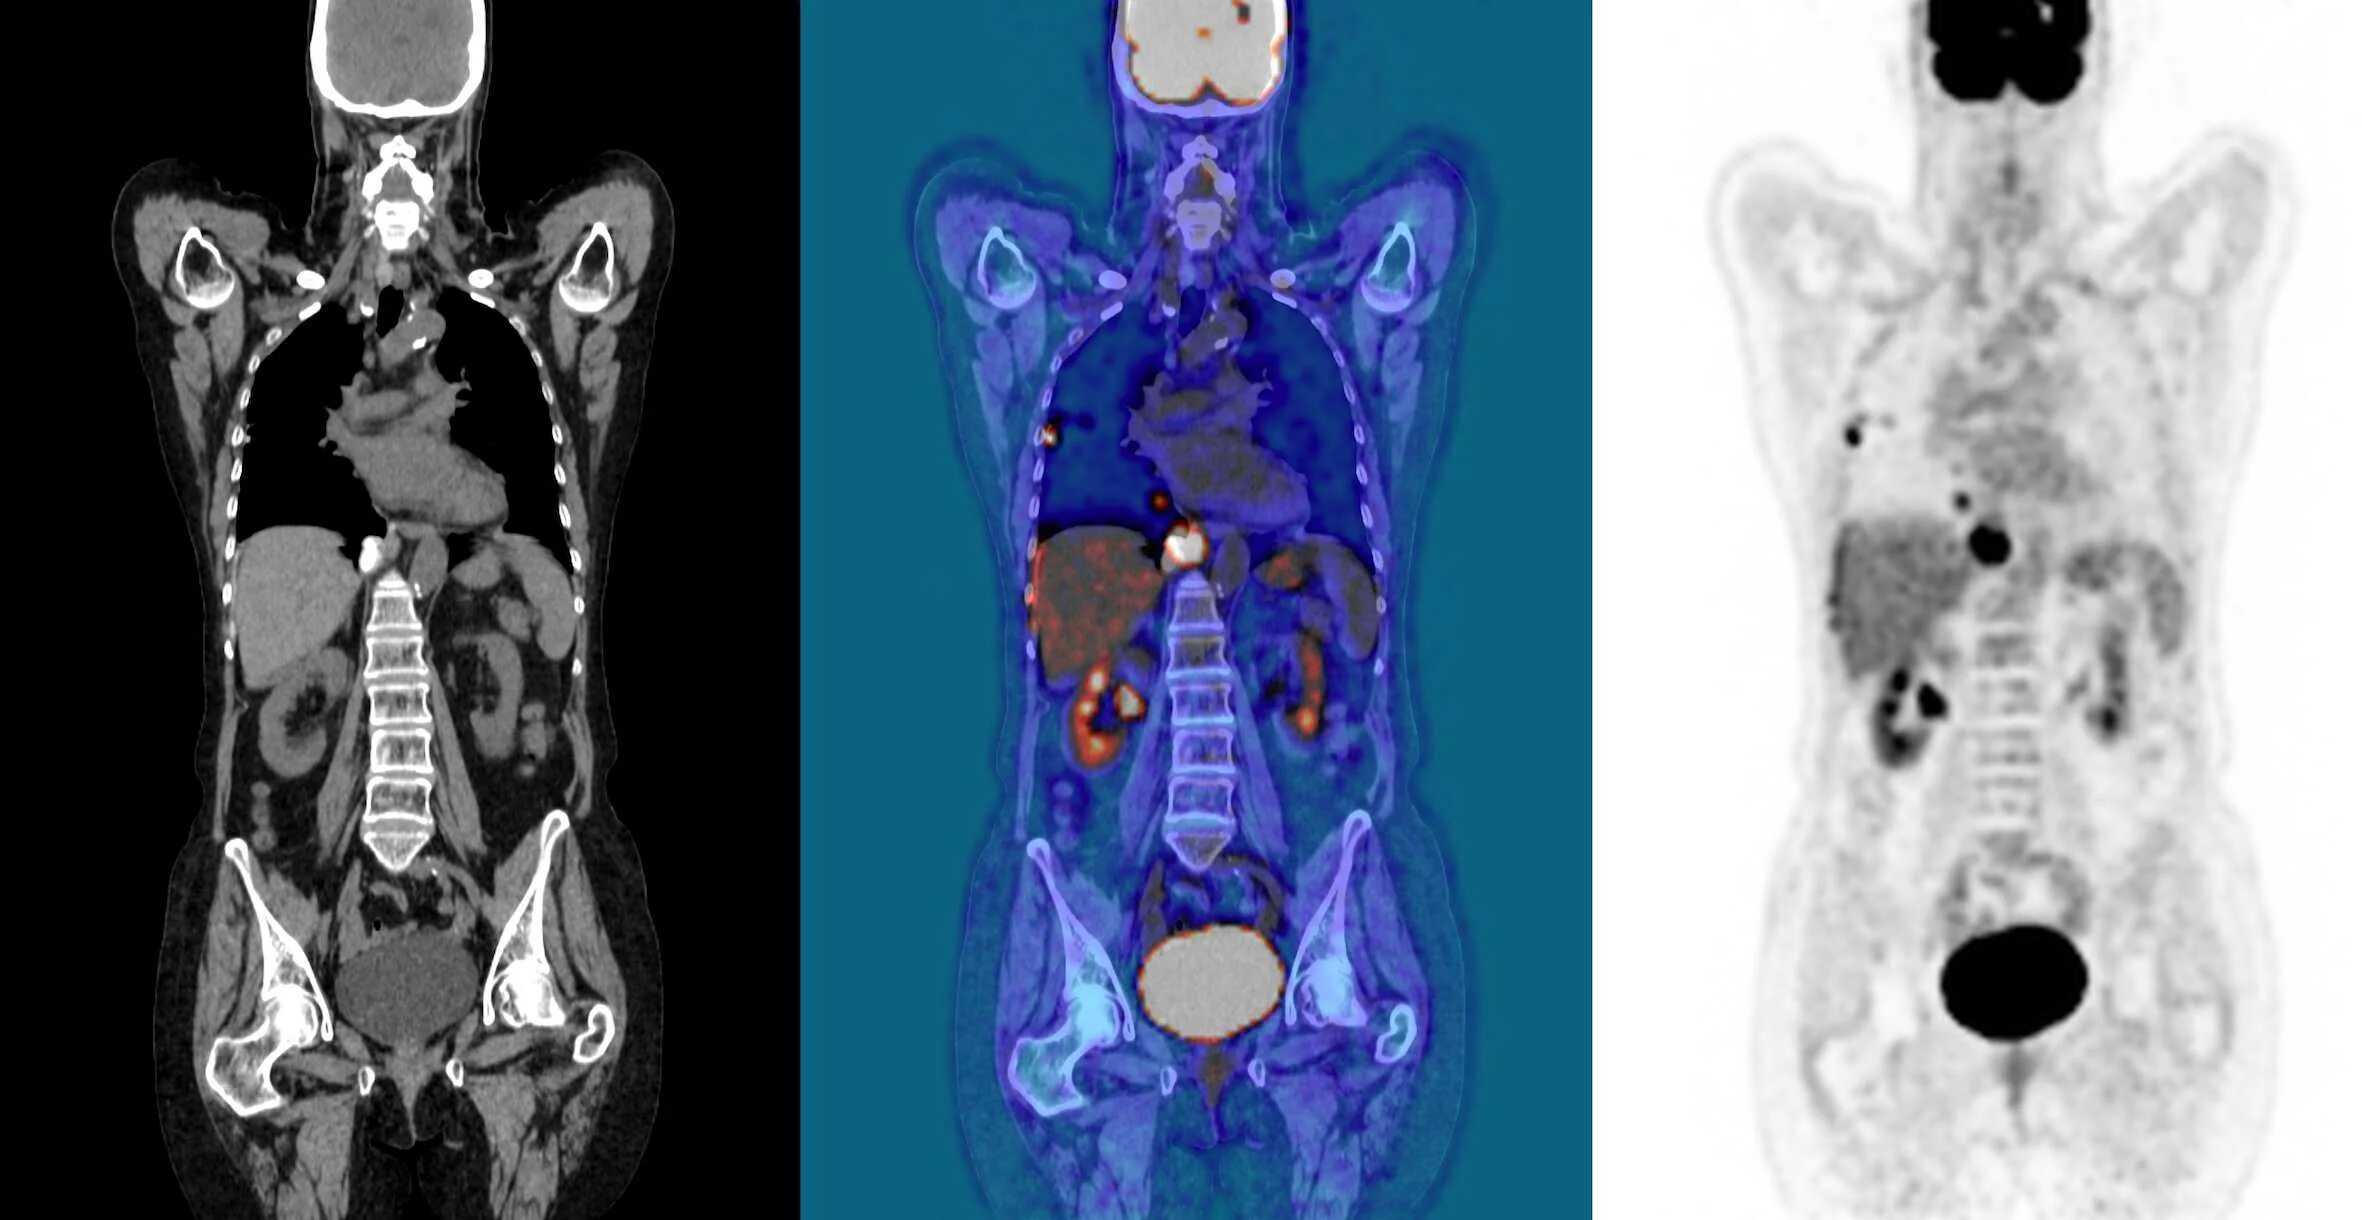

Кт делают с контрастом или нет